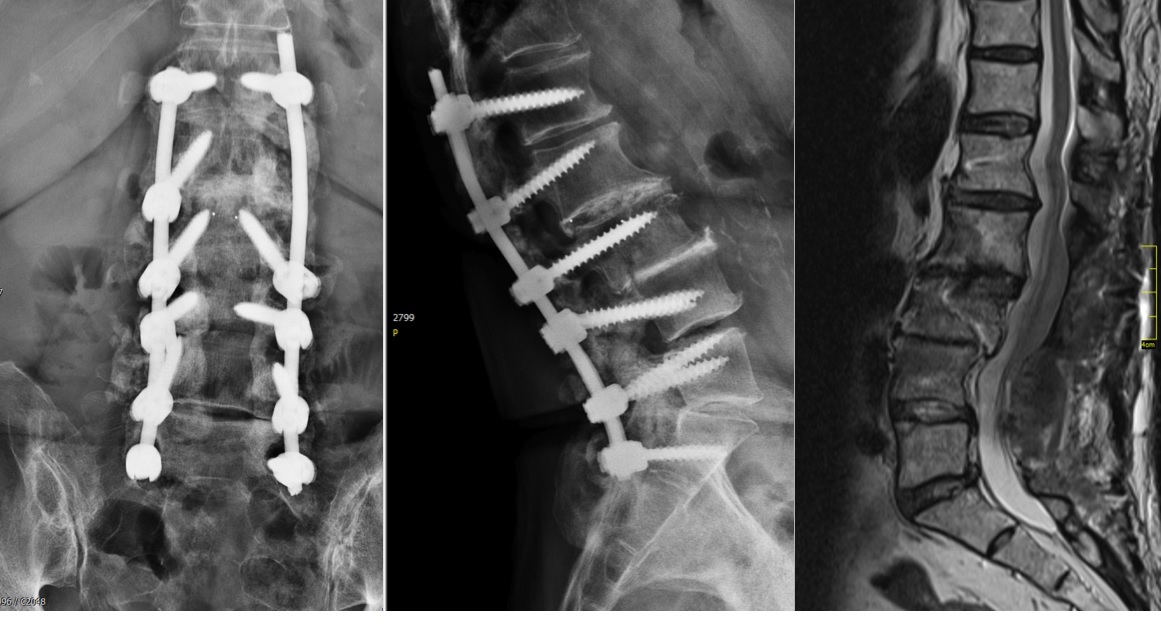

A 75-year-old female patient presented with postoperative back pain. She had been initially operated on eight years earlier with a laminectomy and fusion from L2 to L4. This proved to be successful for a number of years until a second operation was required for secondary back pain and left side leg pain. An extension of the decompression was performed with stabilization and fusion from L1 to S1. The rationale for this operation was unknown and the surgery failed to improve her symptoms.

The problem to be addressed was the patients back pain and left side leg pain, inclusive of some weakness in her left foot. The pain was present upon weight-bearing, with a pain scale of 9. Her discomfort remained at night. The patient was of slim build and was in good general health. She presented with a limp from her left hip and the dorsiflexion of the left foot was weak (M4).

The preoperative standing image of the lumbar spine revealed a flat back with no obvious degeneration of the adjacent segment L1/L2 (Fig 6ab). The implants seemed regularly placed. After wide laminectomy, the spinal canal was open over the whole lumbar spine, illustrated on the MRI scan (Fig 6c).

A CT scan allowed a more detailed assessment (Fig 7). There was an obvious nonunion at L5/S1, with loose screws in the sacrum (red circle). Furthermore, there was instability at L4/L5 as the intervertebral disc presented with an important vacuum phenomenon (asterisk). Foraminal stenosis at L5/S1 (not shown) seemed to be the reason behind the persistent leg pain.

The treatment plan was an anterior height restoration and fusion of L5/S1 and L4/L5. A posterior revision surgery was not considered due to the wide decompression and obvious scar formation. For the correction of level L4/L5, an oblique anterolateral approach (OLIF) was selected due to considerable calcification of the aorta and the iliac vessels. At the L5/S1 level, a straight anterior approach was selected and an additional plate fixation (ATB) was performed.